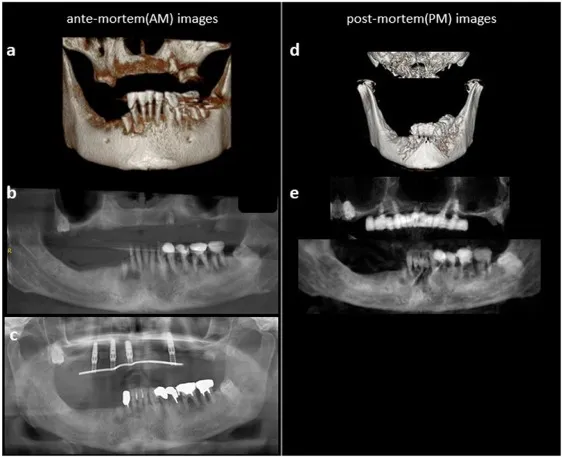

- Core method: Matching digital ante-mortem (AM) with post-mortem (PM) dental data.

- Digital Radiography: Intraoral X-rays, OPGs, crucial Cone Beam CT (CBCT) for 3D views.

- Software Assistance: For image enhancement, superimposition (e.g., Adobe Photoshop, specialized tools), feature matching, and geometric analysis.

⭐ CBCT provides distortion-free 3D images, crucial for complex superimpositions in identification and detailed analysis of bite mark morphology, enhancing reliability.